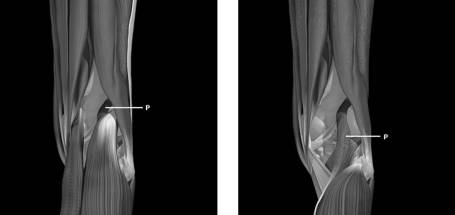

Some photos of plantaris muscle anatomy & position. Its rupture is confused with other causes of calves swellings.